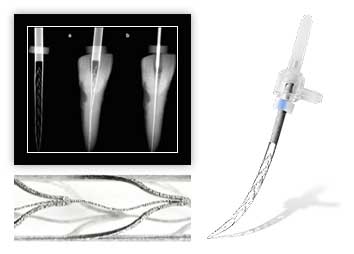

Наше оборудование